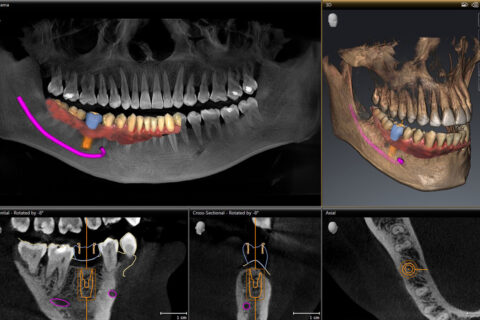

Haben wir das digitale Abbild Ihres Kiefers erstellt, können wir in realistischem 3D die Implantate am PC computergestützt planen. Bei der sog. computergestützten 3D-Implantatplanung ermöglicht uns die Software, die perfekte Position, den idealen Winkel und auch die optimale Tiefe für Ihre Zahnimplantate zu finden, immer unter Berücksichtigung des Knochenangebots, das bei jedem Menschen anders ist. Außerdem haben wir bei der Planung von Zahnimplantaten so auch die Nachbarzähne im Blick und können kritische Strukturen wie Nerven, Kieferhöhle und Nasenhöhle sicher umgehen. Erst wenn wir die Implantation erfolgreich am Bildschirm simuliert haben und mit dem Ergebnis der digitalen 3D-Implantatplanung zufrieden sind, folgt der nächste Schritt.

Quelle: Dentsply Sirona